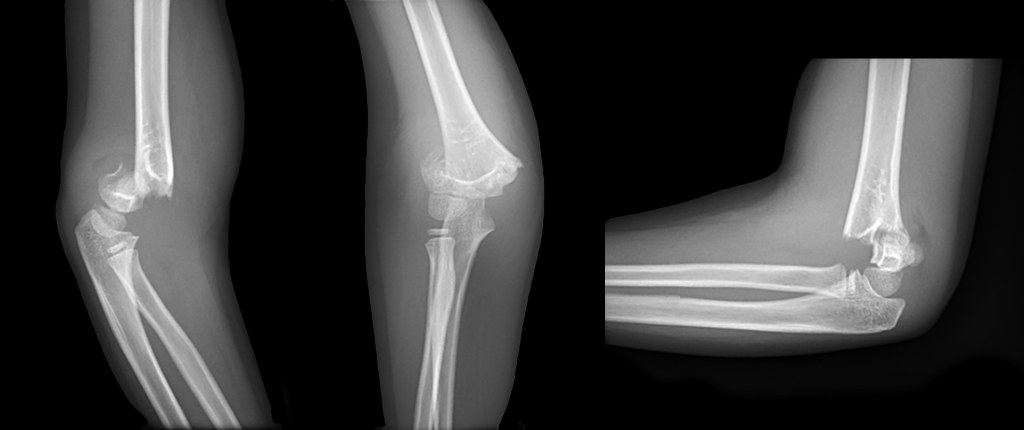

A 6 year-old girl fell from the monkey bars on her outstretched arm, what's the diagnosis? (scroll down for answer)

Answer: Type III supracondylar fracture